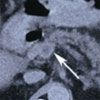

Repeated abdominal CT showed thrombosis of the superior mesenteric vein and fluid around the spleen (Figure 1). The thrombus extended into the portal vein. An abdominal angiogram demonstrated thrombosis of the superior mesenteric vein as well as diffuse venous collaterals, consistent with subacute mesenteric venous thrombosis (Figure 2).